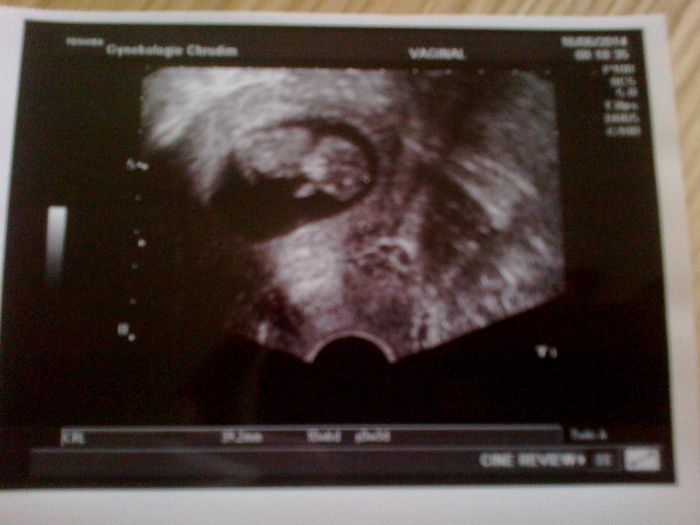

Ahoj holky...tak jsem dnes raději taky zašla k doktorovi, kvuli te me strevni chripajzne a mimisek je v pořádku, je 10+6, má 39mm, pěkně se tam vrtěl a srdíčko mu bilo jako o závod, zase fajn pocit ho po takové době vidět:-) zkusim nahrát fotku, jestli se mi to podaří...

[567807] jj bylo to super, jak se tam vrtelo, jak snad kdyby mu vadilo, že tam na nej vaginálním UZ koukáme, byla to sranda